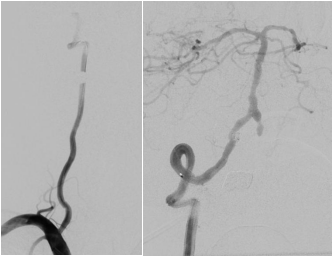

第二步,处理动脉瘤,拆除不定时炸弹。医生将微导管超选择进入动脉瘤腔内,依次填入数枚弹簧圈,直至动脉瘤完全栓塞,不再显影。因为动脉瘤瘤颈宽,故于载瘤动脉内植入了支架以达到致密栓塞,降低复发率。

第四步,最终验证。再次造影显示:狭窄消失,支架位置良好。动脉瘤不显影,弹簧圈致密填塞。